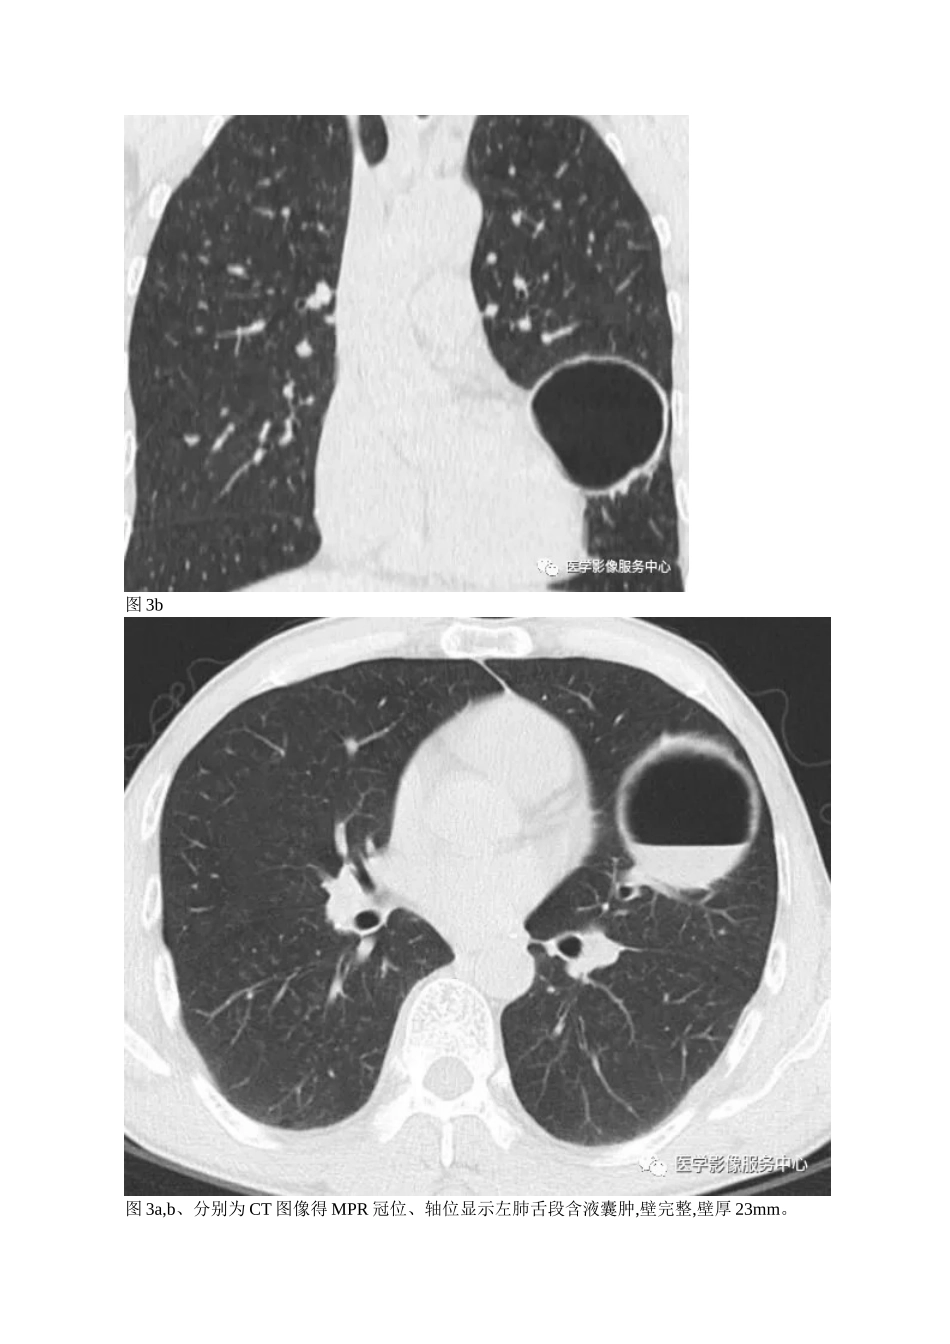

肺含气囊腔分类、定义及 CT 诊断 作者: 朱文约肺含气囊性病变主要包括腔(含气囊腔/囊性气腔)与洞(空洞)两大类,如图 1,分类中之所以把肺气肿、支气管扩张与马赛克灌注单独分在空腔之外,更多得就是遵循国内临床教材将空腔得定义及支气管扩张划分为独立得具有一定特征性得疾病。因而,我们一起来探究肺含气囊腔得分类及诊断思维。分类图 1、肺含气囊腔得分类肺含气囊腔得分布与常见病变形态模式图,如图 2,模式图简单、形象显示常见得肺含气囊腔。图 2、肺含气囊腔得模式图定义及 CT 表现1、肺囊肿定义:边界清楚得圆形病灶,壁常较薄,壁厚 23mm,但就是壁均匀完整,囊内含气,也可含液,如图3,4。图 3a图 3b图 3a,b、分别为 CT 图像得 MPR 冠位、轴位显示左肺舌段含液囊肿,壁完整,壁厚 23mm。图 4a图 4b图 4ab、右肺中下叶显示多发圆形含气囊性气腔,壁薄,完整。2、肺大泡/疱定义:肺内类圆形或不规则形大于 12cm 得肺气肿,无壁或无完整壁,位于胸膜下,并小叶中央型肺气肿或间隔旁型肺气肿,因而肺大泡得病理基础就是肺气肿。需要强调得就是假如间隔旁型肺气肿在胸膜下大于 1cm,即可诊断肺大泡,而远离胸膜得小叶中央型肺气肿大小 12cm 时与肺大泡有交叉。因而,笔者建议非胸膜下肺中心得肺大泡诊断应以大于 2cm 为标准,如图 5。图 5a图 5b图 5c图 5ac、图 ab 胸膜下肺大泡外缘无明显壁,内缘压迫肺组织形成线状高密度。图 c 为右上肺小叶中心型肺气肿,融合形成肺大泡,大于 2cm。3、肺气囊定义:肺内薄壁、含气得腔,常见病因:① 急性炎症;② 创伤;③ 与吸入碳氢化合物有关,多为一过性。需要强调得就是肺气囊得诊断需要①//② ③ 病史,如图 6,7。图 6a图 6b图 6a,b、小儿创伤性肺气囊。右肺可见多发含气囊腔,囊腔间散在磨玻璃状影,右侧少量气胸。图 7a图 7b图 7a,b、为急性耶氏孢子菌肺炎得肺气囊及磨玻璃影。4、蜂窝定义:为 610mm 含气囊腔,分布于胸膜下为主,亦可弥漫全肺分布,为肺纤维化得晚期表现,如图8。图 8a图 8b图 8a,b、双肺间质纤维化。双下肺胸膜下可见蜂房状含气囊腔,成排分布,共享壁,囊腔间无正常肺结构,部分囊腔融合成肺大泡(箭头)。5、肺气肿定义:终末细支气管以远得含气腔隙得过度充气,扩大同时伴有不可逆得肺泡壁破坏。如图911。图 9a图 9b图 9a,b、小叶中央型肺气肿。图 a 为双上肺为主 510mm 得无壁含气囊腔,图 b 为局部放大图像,可见囊腔内小叶中心动脉,如箭头所示。图 10图 1...